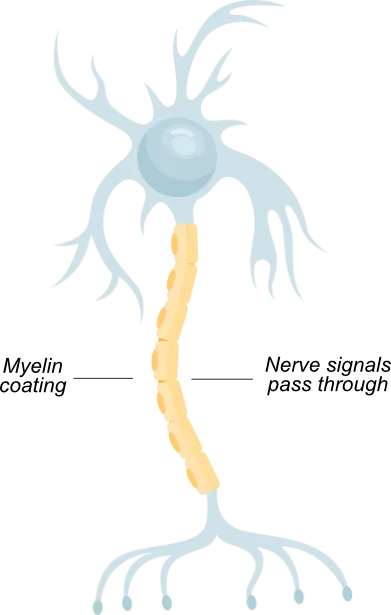

Why MS OCCURS

MS is an autoimmune disease that damages the myelin coating around nerve fibres, causing disruption of nerve signals

This disruption can cause problems with vision, movement, strength, coordination and thinking

In a healthy neuron, myelin protects nerve fibres, like insulation around a wire